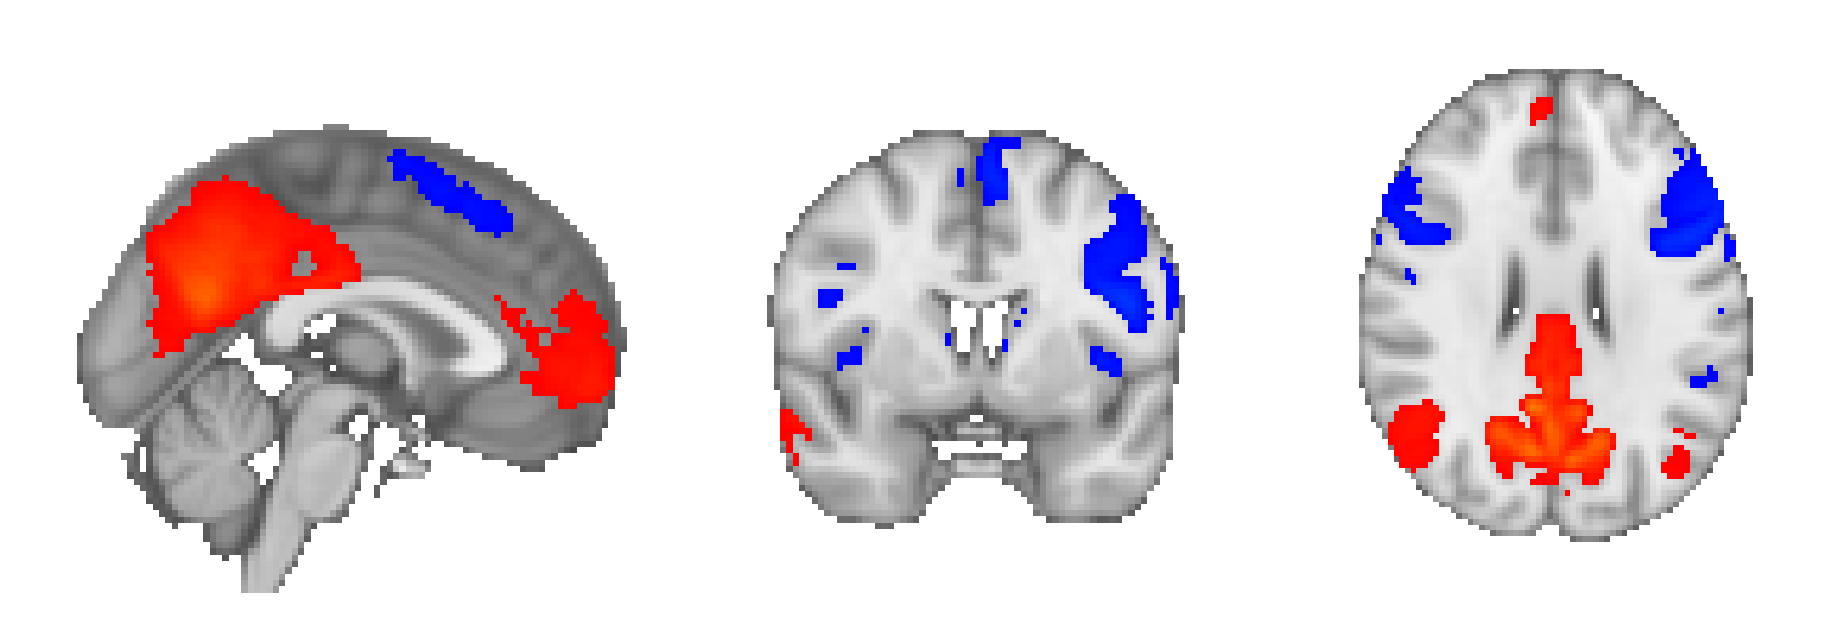

Figure 2 displays one of the hierarchical components with coarse-scale component storing relation between different fine-scale components comprising DMN, sensorimotor, and visual areas, previously studied by [40]. These findings give evidence that even after removal site effects, the components can have a meaningful interpretation. The results indicate that our approach can extract robust informative patterns without using traditional seed-based methods that are dependent on the knowledge of the seed region of interest.

We computed spearman correlation of age () with and . We then calculated p-values for the hypothesis test of no correlation against the alternative hypothesis of a nonzero correlation and are converted to , where is log base . Table 15 and 16 displays spearman correlation and negative log -value. The total number of subjects with age greater than is . In the case of negative log base 2, if the value is greater than then we consider it statistically significant, equivalent to -value less than . Figure 5 shows anti-correlation between DMN, and Salience Network (SN) and Central Executive Network (CEN), and negative correlation with age. Previously, Nagel et al. [83] has found a decrease in the functional coupling between DMN and the premotor cortex, corroborating our results.